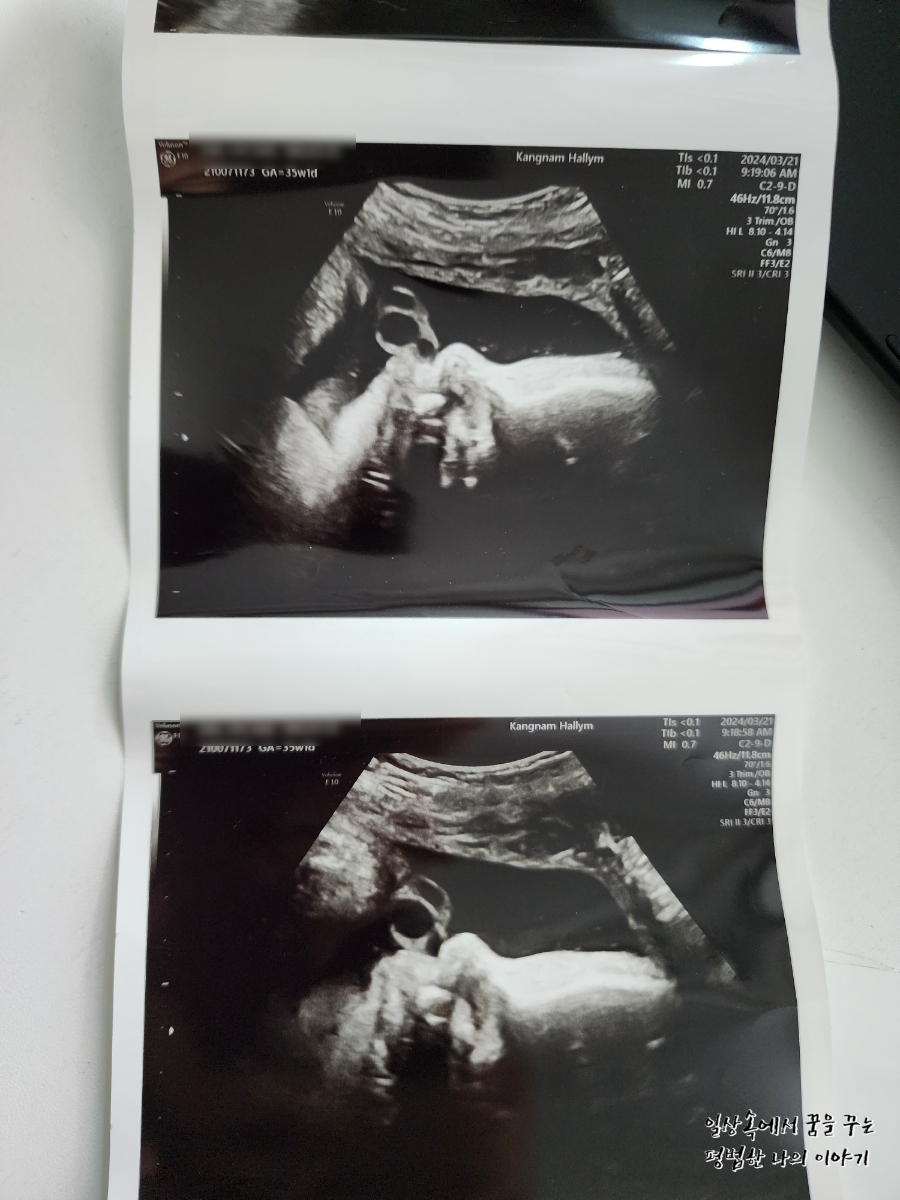

3주 만에 방문한 병원에서 딸내미는 더욱 커져서 35주 차에 첫째 37주 차 때 사이즈와 모든 게 비슷해져 있었다.(머리둘레, 배 둘레, 몸무게 등) 첫째를 꽉 채운 40주 차에 유도 분만으로 출산했는데 4.09kg으로 무척 커서 출산하고 의료진과 함께 놀랐던 기억이 있다. 둘째는 이를 훨씬 앞서고 있으니 의사 선생님도 40주까지 기다리는 건 무리가 있다고 생각하시는 것 같다. 나는 38주 차에 유도 분만을 하고 싶으나 의사 선생님은 39주까지 채우고 유도 분만 하기를 권하셨다. 우선 나의 몸이 아무런 준비가 되지 않았기 때문에 유도 분만이 실패할 가능성이 있어 38주보다는 39주 차를 더 선호하시는 것 같다. 나는 첫째가 4.09kg으로 태어난 탓에 우량아라 인큐베이터에 일주일이나 있었던 게 싫었던지라 이번에는 어떻게든 4kg 미만으로 아이를 출산하여 나와 함께 퇴원하고 싶은 마음이 크다. 그러면서도 최대한 유도 분만을 하고 싶고 제왕절개로 상황이 흘러가게 되는 건 또 싫어 고민이 많다. 여태까지 나의 몸무게는 9kg 정도 늘었는데 첫째 때보다는 양호한 수준이다. 그래도 또 알 수가 없는 게 막달에 일주일에 1~2kg은 쉽게 몸무게가 늘기 때문에 첫째 때만큼 살이 찐 상태에서 출산할 가능성도 없지 않다.